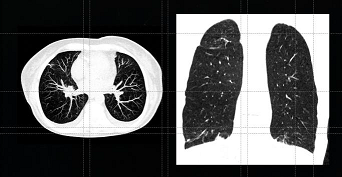

シーメンス製CT装置のフラッグシップモデル「SOMATOM Force」や「SOMATOM Drive」に搭載されているX線スペクトラム変調技術を「SOMATOM go」にも搭載した。この技術は画像化に寄与しない低エネルギー成分のX線を効果的にカットし、一般的な胸部レントゲン撮影と同等の被ばく線量*によるCT検査を可能にする。本技術は現在までに胸部低線量肺がんスクリーニング検査にも利用されており、人間ドックや健康診断への適応も期待される。

Courtesy of Medical University of Erlangen, Germany